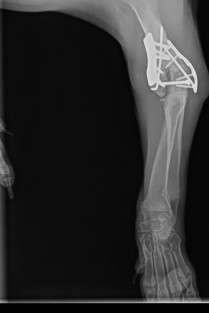

Rééducation post-opératoire des pathologies du coude